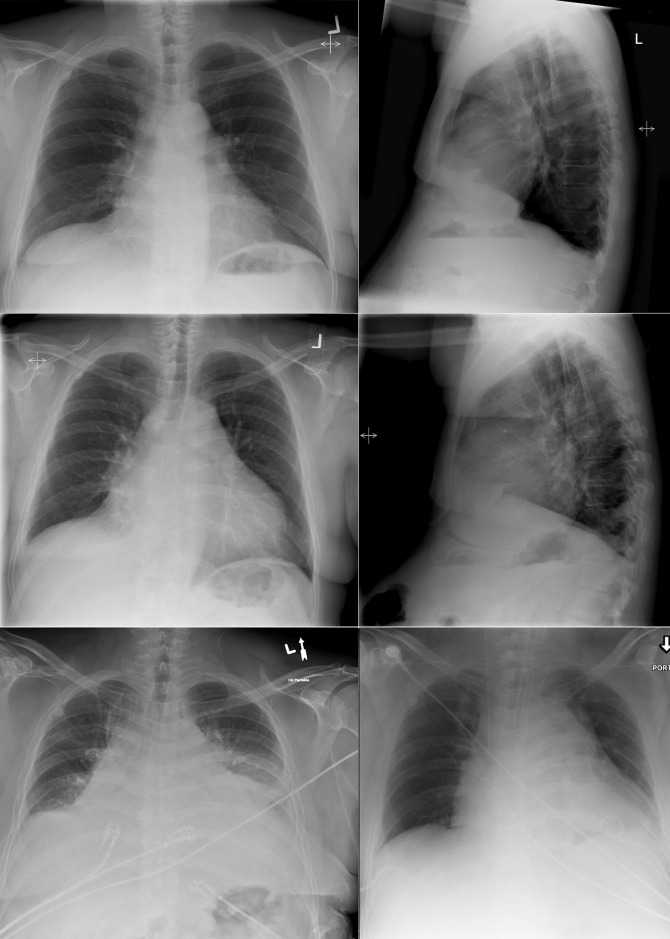

A pericardial effusion ( Figs. 16-1 to 16-15 ) is often suggested on the frontal chest radiograph by a smoothly distended, “flasklike” CPS. More than 500 mL of fluid must be present before the change in the CPS is fairly obvious. A flasklike appearance may be caused by myocardial disease as well; scrutiny of the hilar vessels may distinguish the two. In the presence of pericardial effusion, the hilar vessels are covered (the pericardium runs up onto them and obscures them). In the presence of myocardial disease, the hilar vessels are unusually prominent as they are distended under higher than usual pressure.

In a minority of patients with pericardial effusion, on the lateral radiograph, a stripe of radiolucent epicardial fat, a “fat line,” may be visible anteriorly, suggesting fluid in the pericardial space. A stripe greater than 2 mm is abnormal. This “pericardial stripe sign” is more easily seen in adults than children (more fat!).

A prominent azygous vein, superior vena cava, or inferior vena cava suggests cardiac tamponade.